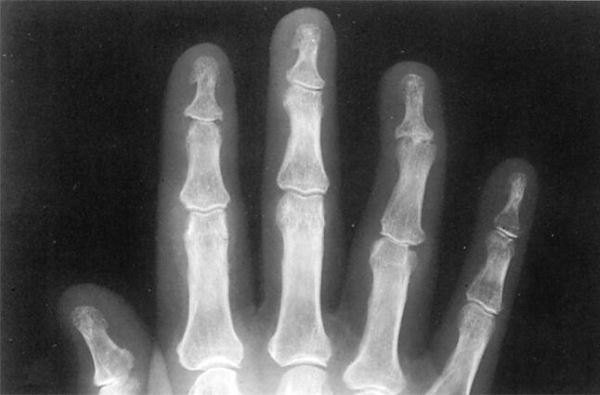

- Артрит, затрагивающий дистальные межфаланговые суставы. Основные нарушения и изменения определяются именно в суставных тканях пальцев;

Реже поражаются крупные тазобедренные суставы. Артрит часто асимметричный. Кроме того, специфической особенность этого артрита является развитие т.н. осевого артрита пальцев (т.е. поражаются все суставы одного пальца), и развитие дактилита. Под дактилитом (от греч. “dactylos” — палец) понимают воспаление пальцев, которое проявляется выраженной болью, ограничением движения, отек и припухлость пальца. За счет осевого артрита и дактилита пальцы приобретают характерный “сосискообразную” форму.

- Если ассиметричный артрит поражает кисти и стопы, воспаление и припухание сухожилий может вызвать характерное утолщение пальцев (дактилит), и они становятся похожими на маленькую сосиску («сосискообразные» пальцы).

Для артрита, поражающего дистальные межфаланговые суставы, характерна наиболее типичная для этой патологии клиническая картина. Пальцы рук и ног отекают, кожа краснеет и становится горячей на ощупь. Болезненные ощущения возникают не только в дневное время, но и ночью, еще более ухудшая психоэмоциональное состояние человека.

- Суставы стоп, кистей могут быть припухшими, болезненными, оттенок кожи над ними синюшный, с багряным отливом, такие пальцы образно называют сосискообразно деформированными.